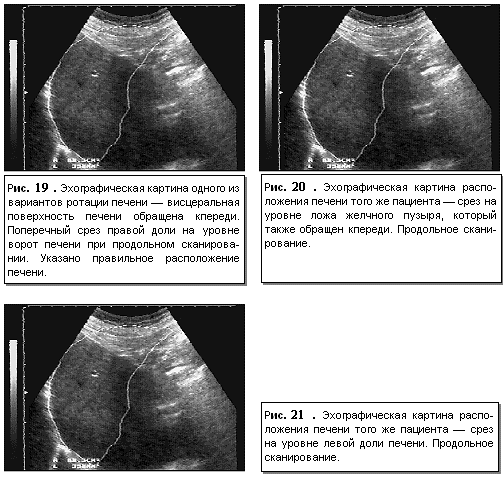

Ведя разговор об ультразвуковой анатомии печени, нельзя не отметить возможные анатомические варианты развития, которые в некоторых случаях могут имитировать те или иные патологические состояния. К таковым анатомическим вариантам развития печени относятся: инверсия печени, ротация печени, вариация контуров и размеров долей, доля Риделя, истончение левой доли, врожденное отсутствие левой доли, локальная гипертрофия долей и сегментов печени, дополнительные борозды, интерпозиция толстой кишки и т.п. Инверсия печени – расположение органа в ином месте брюшной полости – чаще всего в левом подреберье, сочетающееся с инверсией прочих органов пищеварительной системы. Ротация печени – изменение ее расположения вдоль одной из осей – длинной или короткой. Чаще наблюдается вариант ротации по длинной оси, при котором к передней брюшной стенке обращен не нижний край печени, а либо висцеральная, либо диафрагмальная поверхности (рис. 19-21).